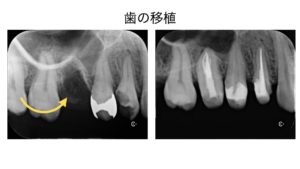

ただし、親知らずの中でも普通の歯と同じように生えていて、歯ブラシの届く範囲できれいに噛み合っている歯は保存することも可能な場合があります。

また条件が揃えばですが、使えなくなった奥歯の代わりに親知らずを移植して使用することも可能です。